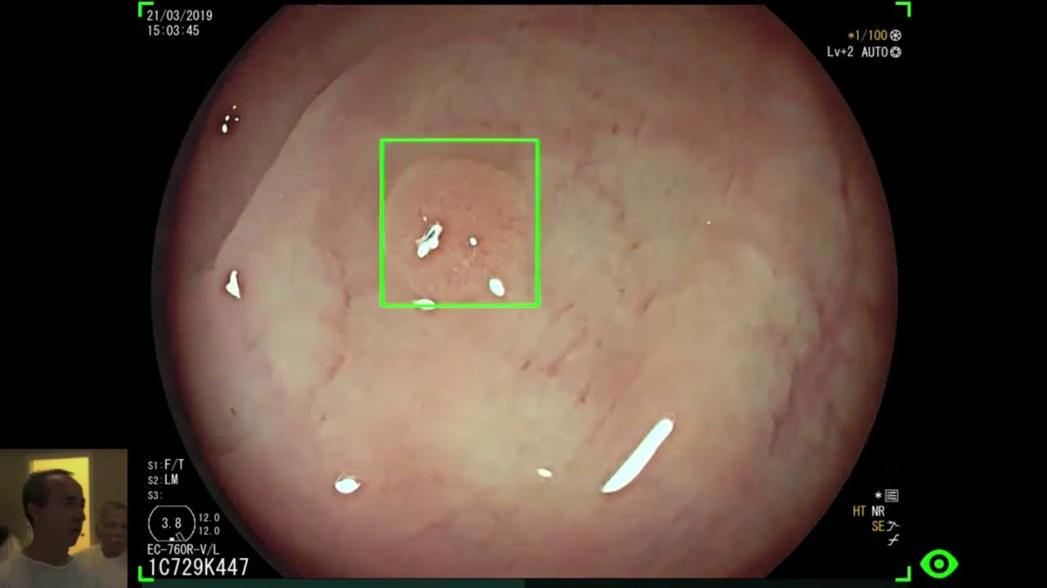

GI Genius обрабатывает данные колоноскопии в режиме реального времени, используя свой алгоритм для автоматического выявления полипов толстой кишки всех форм и размеров. Модуль разработан для подключения к стандартному эндоскопическому оборудованию всех основных брендов.

В ходе исследования при использовании системы искусственного интеллекта во время обследования было пропущено всего около 15% полипов, в то время как при колоноскопии без искусственного интеллекта этот показатель составил более 32%.

GI Genius имел значительно меньший процент пропусков, чем стандартные методы практически по всем пунктам сравнения: он заметил больше полипов в каждом из проксимальных и дистальных отделов толстой кишки, а также больше полипов крошечного размера и менее заметных на слизистой оболочке толстой кишки.